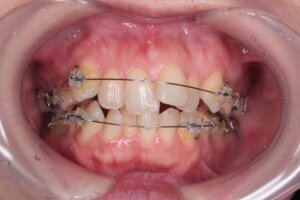

抜歯をした直後の状態です。

抜歯が終わり、いよいよブラケット装着。

しかし、前歯部の重なりが大きく前歯部にはブラケットをまだ付けることが出来ません。

まずは、抜歯をしたスペースに向かって歯を移動させていきます。